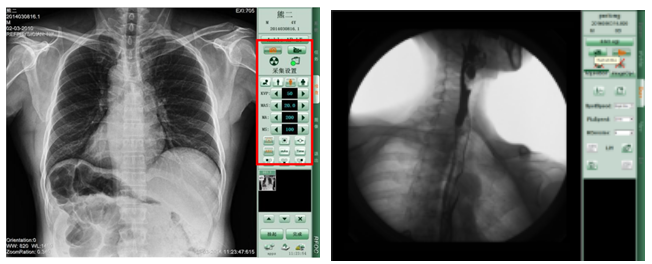

PLD7600平板动态DR拍片效果-普爱医疗